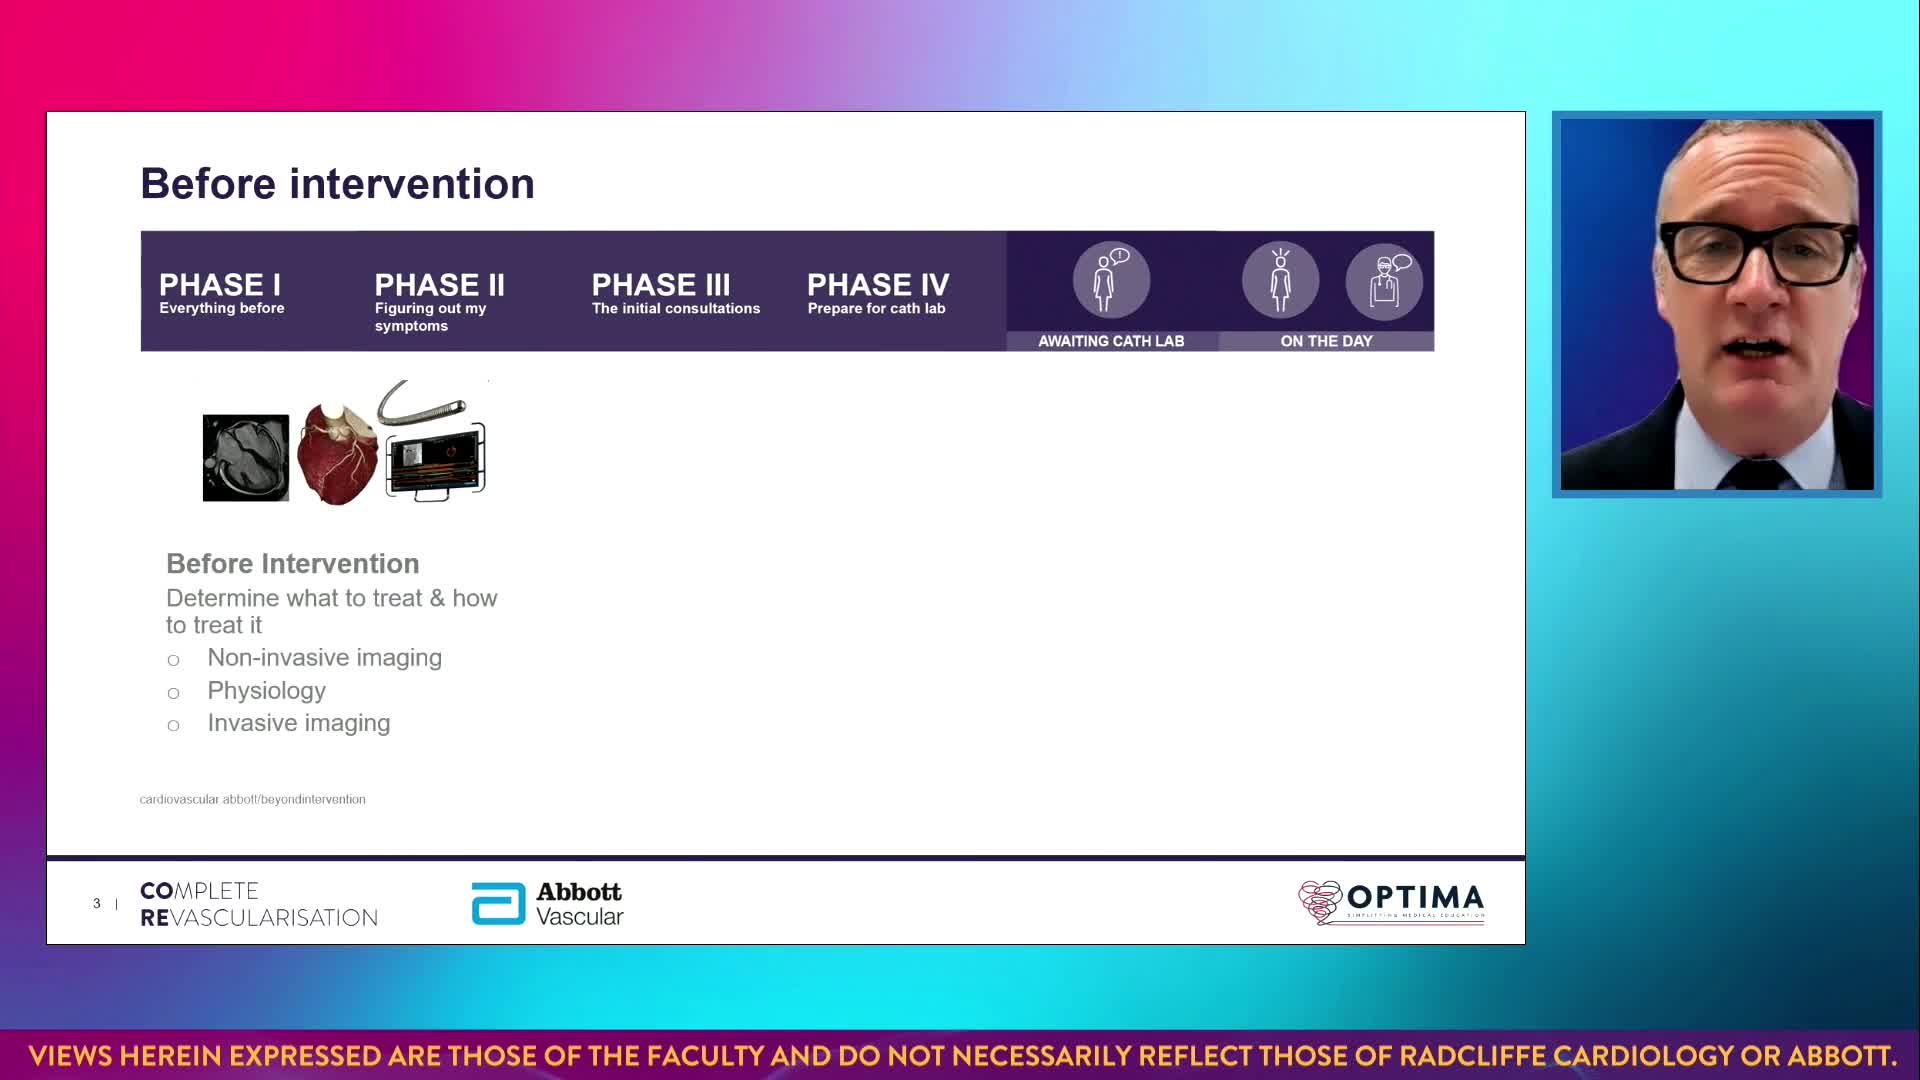

Session 1: Pre-procedure planning – are we lost without a map?